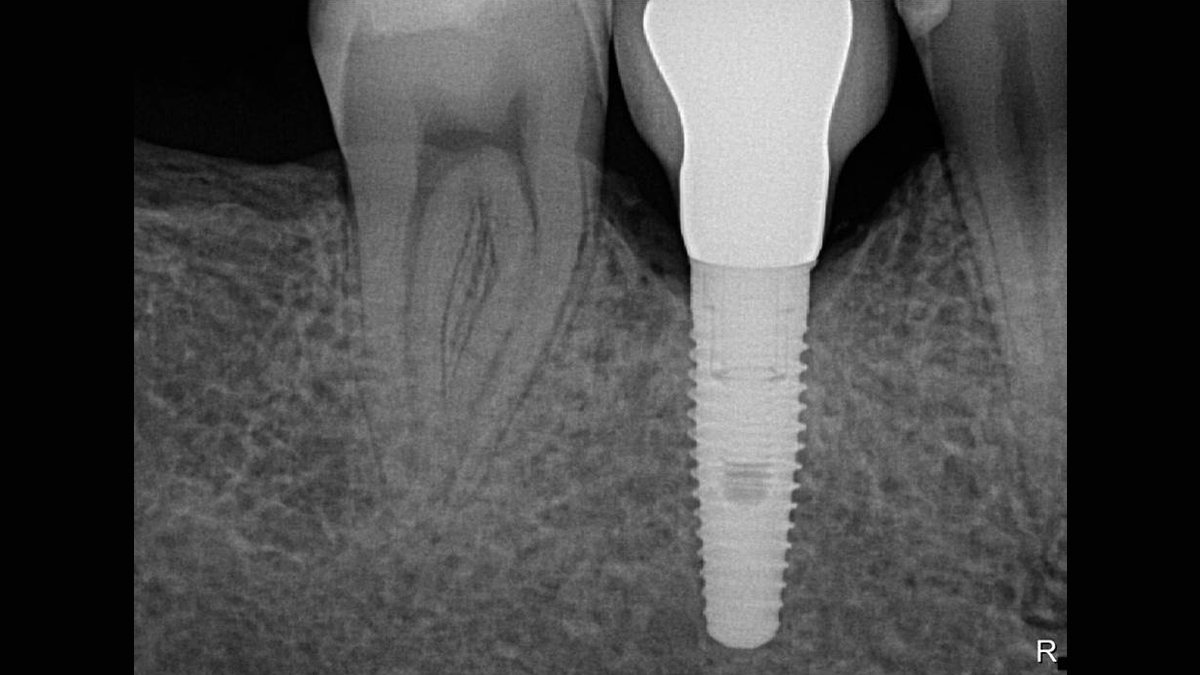

Los sensores intraorales de Dentsply Sirona proporcionan calidad de imagen de vanguardia que apoya el diagnóstico preciso del tratamiento y visión clara de la situación clínica. Respaldado por elecciones expansivas del sistema, mejora de filtro de imagen y servicio de vanguardia y personal de apoyo, los sensores intraorales Xios ofrecen varias posibilidades para su consultorio - brindándole beneficio a usted y sus pacientes.